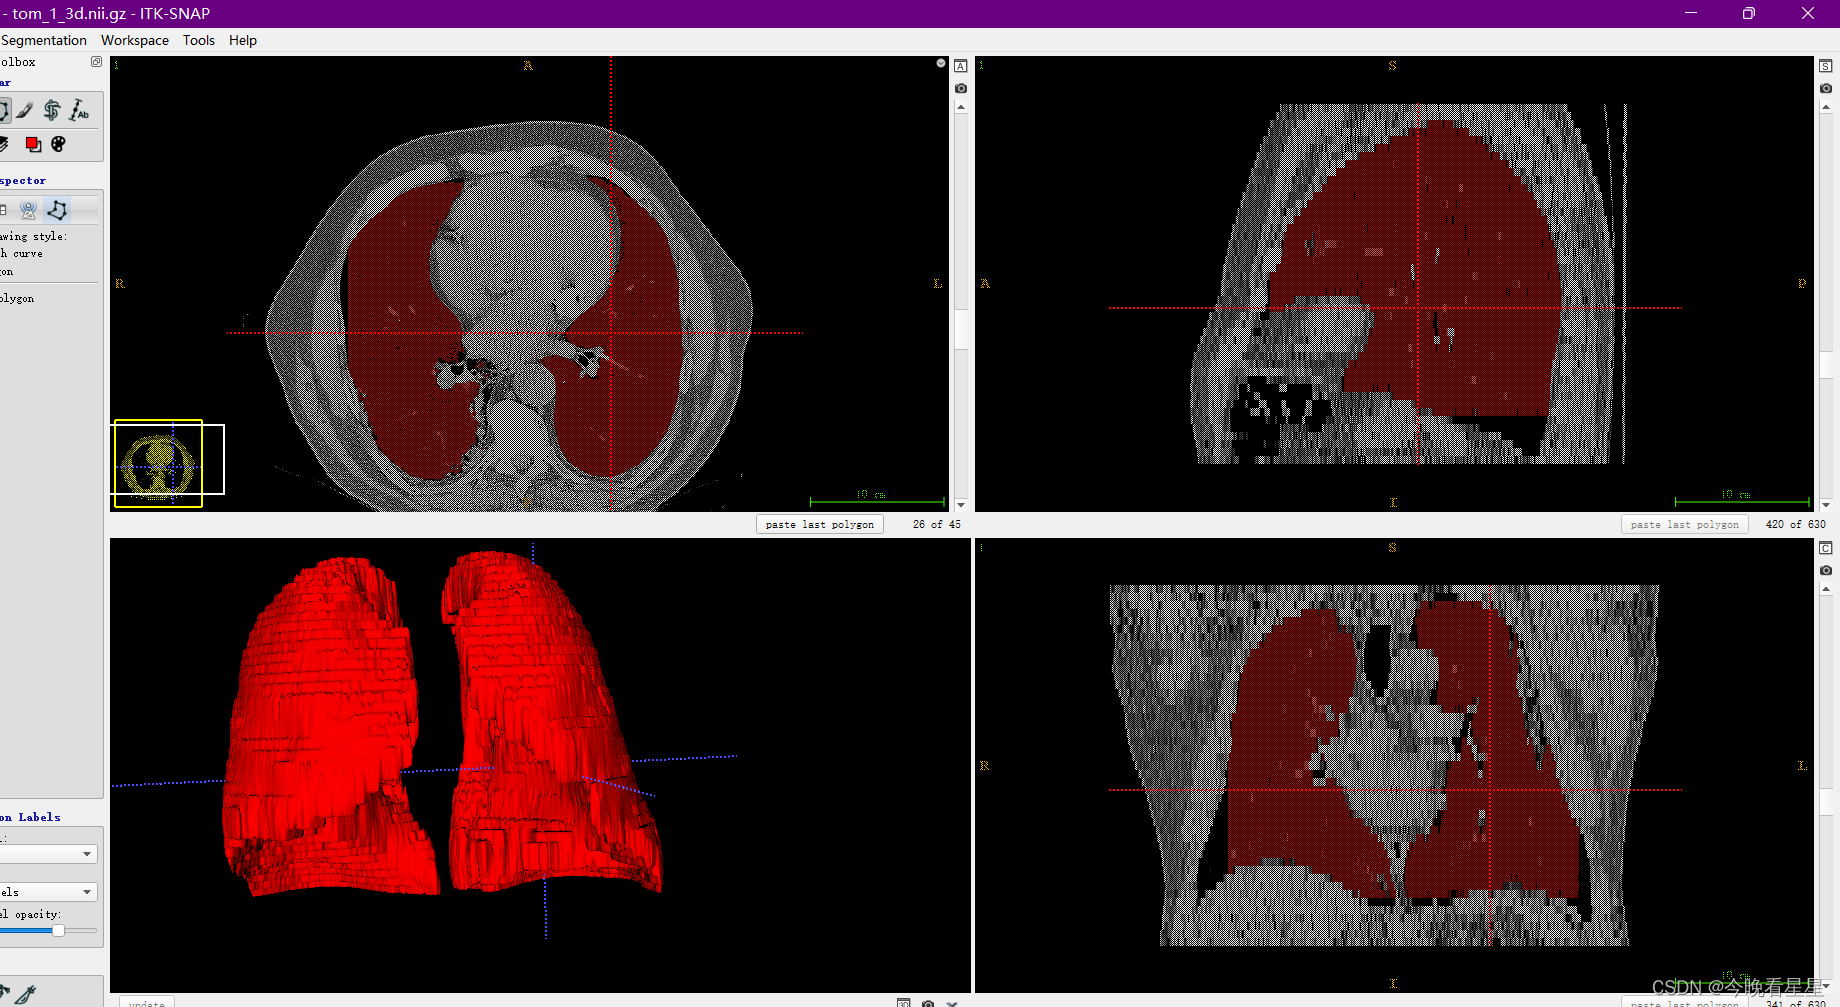

对于处理DICOM的软件有众多,本文章采用ITK-Snap来进行介绍。ITK-Snap的主要功能是对医学图像进行分割,包括2D与3D的分割,包括人工分割与半自动分割。本文主要介绍ITK-Snap的基本使用,包括基本功能的介绍,医学图像的查看以及医学图像的标注

1.1 ITK-Snap视图介绍

在刚开始使用软件的时候,可能上来就被该软件的视图搞蒙了,类似于咱们数学上的三视图,但是他是从CT扫描的视角观察的

三个切片窗口分别为:

- 轴向面(Axial)

- 矢状面(Sagittal)

- 冠状面(Coronal)

常用的有轴向面与冠状面,可以帮助我们进行空间上的定位与标注

Crosshiar Tool即图像中的十字虚线定位点Zoom/Pan Mode用来缩放图像Polygon Drawing Mode多边形勾选区域,可以设定选定的模式,1)使用Smooth curve2) 使用Polygon多边形PaintBrush Mode用来涂画标注的区域Active Contour Segmentation Mode半自动进行区域的标注Annotation Tool可以标注图像上两点之间的距离,

- 最终的效果

- 3D的结果